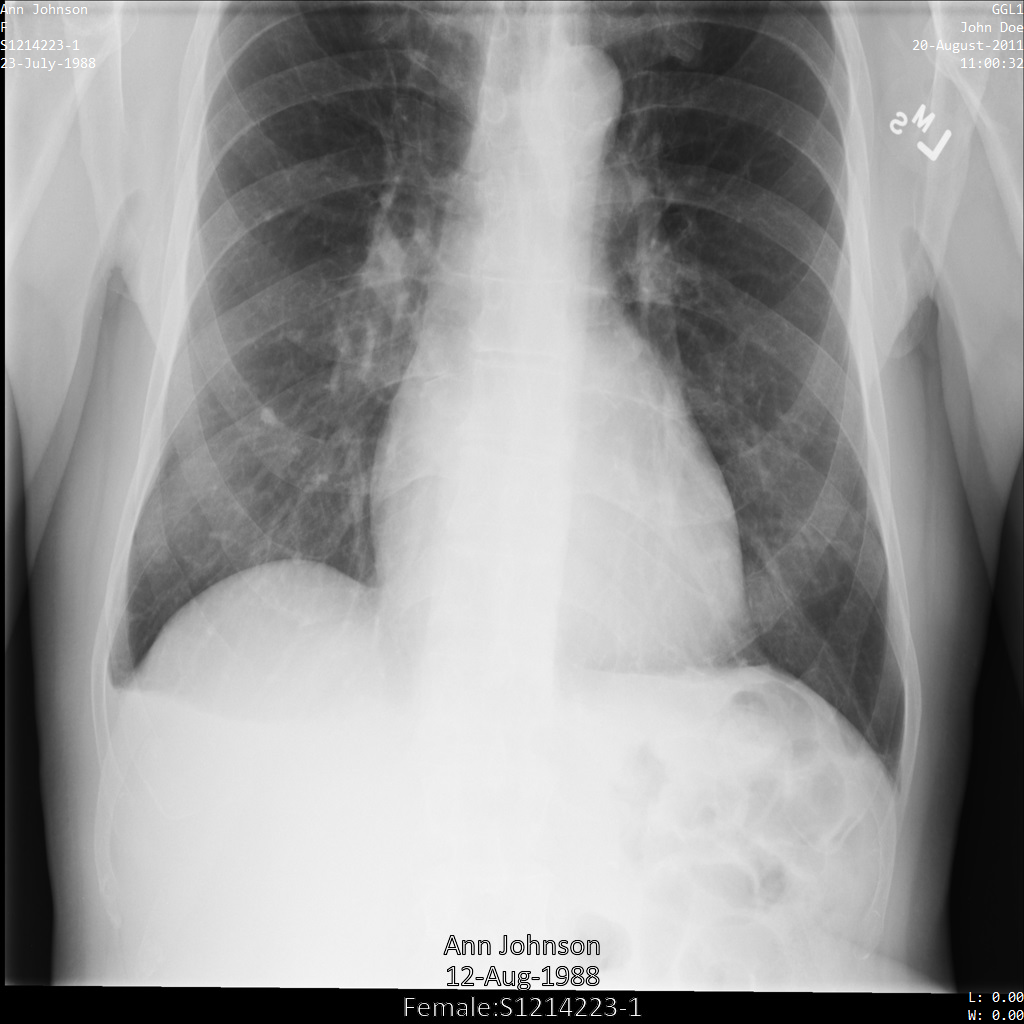

以下各部分提供的示例展示了如何使用各种方法对 DICOM 数据进行去标识化。每个示例都会提供去标识化后的图片输出。每个示例都使用以下原始图片作为其输入:

您可以将每个去标识化操作的输出图片与该原始图片进行比较,以查看该操作的效果。

将图片提交到 Cloud Healthcare API 后,图片显示如下。除了 removelist 中提供的标记之外,便只有 PatientBirthDate 会从图片中移除,因为它是 removelist 中唯一与图片中可见的元数据对应的标记。

虽然图片顶部角落的 PatientBirthDate 已根据 removelist 中的配置进行了遮盖,但图片底部的烧屏 PHI 仍会保留。如需一并移除烧屏文字,请参阅遮盖图片中的烧屏文字。